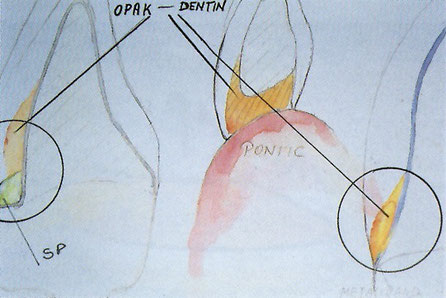

図8 オペーシャス・デンティンの使用法。